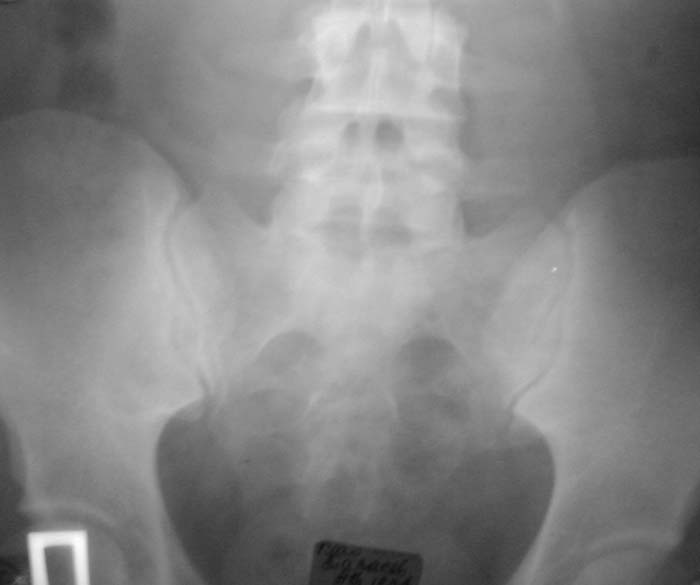

Уважаемые коллеги! Окажите, пожалуйста, консультативную помощь. Мужчина, 24 года. Туберкулез крестцово-подвздошного сочленения справа,

активная фаза. Болен в течение 6 месяцев. Проходил курсы НПВС - без эффекта. Жалобы на постоянные боли в поясничной области. Местно: крестцовая область припухшая, кожа не изменена, при пальпации боль, осевая нагрузка - боль, хромота на правую ногу. Общие анализы - без особенностей. МРТ 09.11.03. - патологических изменений в поясничном отделе не выявлено. Описание рентгенолога: остеосклероз, нечеткость контуров, участки деструкции в правом крестцово-подвздошном сочленении. Положительный анализ на антитела к микобактериям (IgM+E) от 16.10.03. Вопросы: уточнение диагноза, определение тактики лечения. С уважением, А.В.Владзимирский Донецкий НИИ травматологии и ортопедии Донецк, Украина